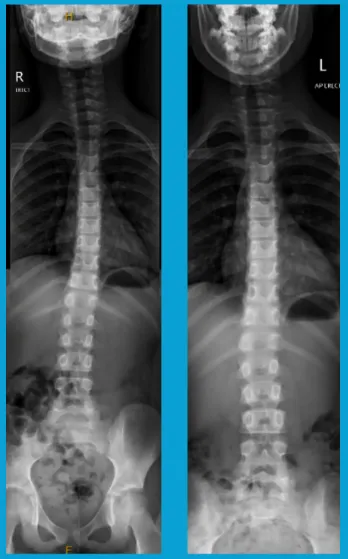

Scoliosis

Stephanie's parents brought her in with concerns about her posture. Examination showed a developing scoliosis which we thankfully caught early and were able to begin reversing her scoliosis over a course of treatment lasting 12 months. Stephanie continues with maintenance care to make sure she continues with a strong and healthy spine over the adolescent